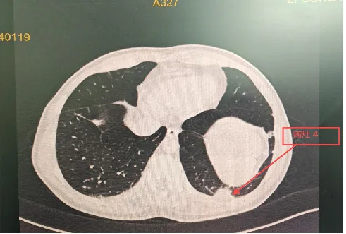

病历检查结果

2天后病理结果出来了—— 机化性肺炎

明确诊断后,主管医师予以相应的治疗方案,程大叔的咳嗽、胸痛症状迅速得到了缓解;1月后复查胸部CT,提示肺部阴影较前明显吸收;程大叔悬着的心,终于放下了。

治疗前

治疗1月后